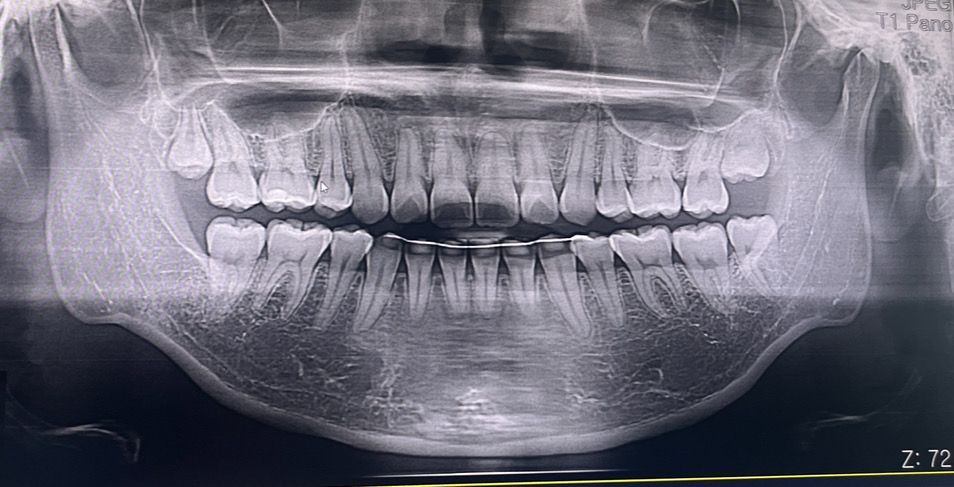

이후에도 일주일 정도 지속되어 다시 엑스레이를 찍어봤고, 신경 상의 문제는 없는 것 같다고 하셨습니다. 교합의 문제일 수 있다고 하셔서 교정 치과에도 다녀왔으나 (앞니 아랫니에 부착식 유지장치를 착용중입니다) 문제가 없다고 하셨습니다.

밥 먹을 땐 통증이 없어 다행이지만 이유를 모르겠어서 답답합니다..... ㅜㅜ 혹시 몰라 엑스레이 첨부합니다,,

잠을잘떄 통증이 더 심하다면 치수염일 가능성이 높습니다. 계속 불편하시면 신경치료를 하셔야될수도 잇을것같습니다.